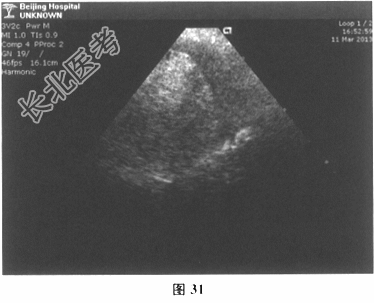

- 多项选择题6.[提示]床旁超声心动图(图31)示大量心包积液,可疑左室室间隔近心尖部破裂。因情况危急, 立即转运至导管室,行左室造影证实为左室室间隔近心尖部破裂。